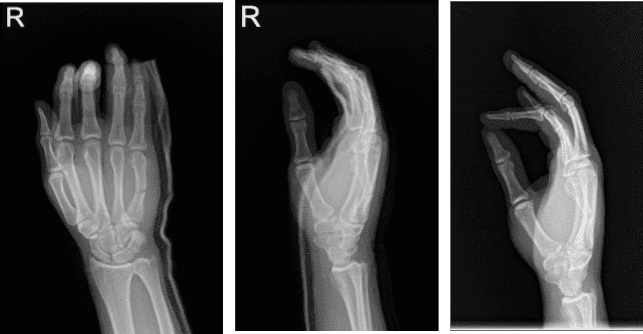

Se presentaron radiografías que mostraron la siguiente impresión: reidentificación de una fractura transversal ligeramente angulada en el metacarpiano medio de un tercio derecho del quinto. Existe un elenco sobrescéntrico.

Dos semanas después de la operación, el paciente llegó con el resultado de su radiografía. Dos clavos atraviesan una fractura no desplazada: un tercio y un cuarto metacarpiano derecho. Se observa una formación de callos leves. La línea de fractura sigue siendo apreciada.

Existe un elenco sobrescéntrico. No hay subluxaciones ni dislocaciones. No hay cuerpos extraños radiopacos. Se observa una leve hinchazón de tejidos blandos. Fractura en cicatrización del quinto metacarpo derecho, como se ha mencionado antes.